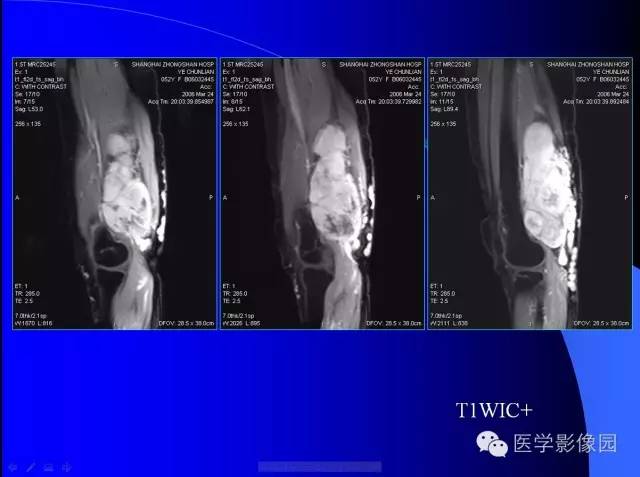

【病例】大腿恶性孤立性纤维瘤1例MR

病史:女,52岁,左大腿包块30年,逐渐长大。

孤立性纤维瘤起源于弥漫分布于人体结缔组织中CD34阳性的树突状间叶细胞。多见于头颈部、上呼吸道、腹腔和周围软组织。发病高峰40~ 60 岁, 女性多见。临床上多数病例表现为局部缓慢生长的无痛性包块。随着包块的增大, 会出现相应部位的压迫症状。孤立性纤维瘤多数病例临床上呈良性经过, 约10% 的非典型性和恶性孤立性纤维瘤局部复发率或远处转移率较高(80% )。